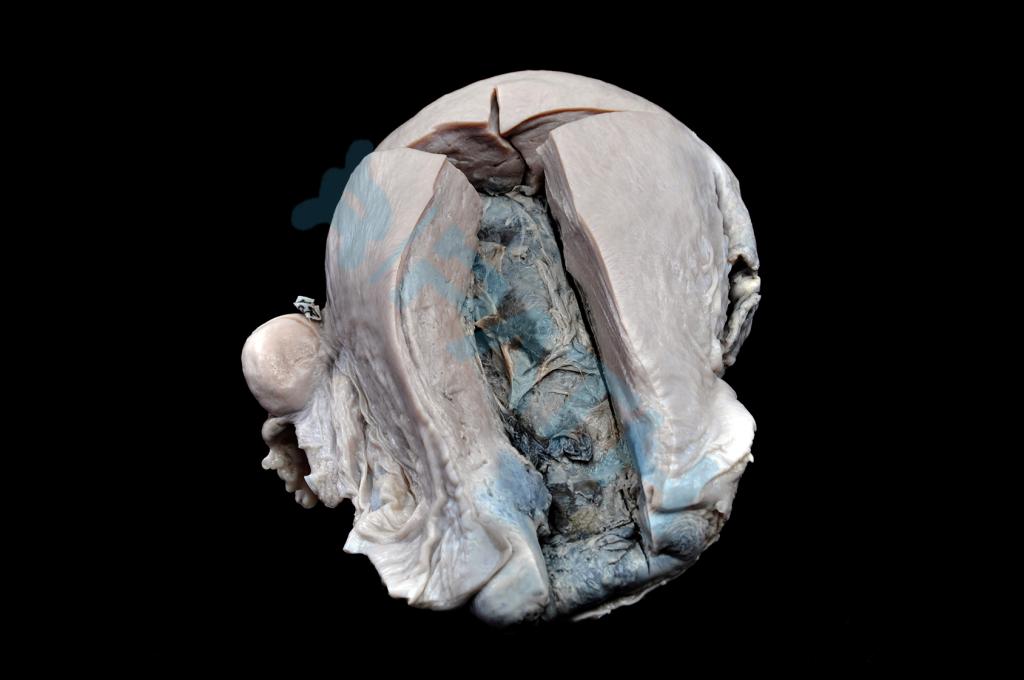

心肌萎缩

肾脏压迫性萎缩

亚急性黄色肝萎缩

子宫肥大(1)

子宫肥大(2)

肝脂肪变性

肾水肿

脾被膜透明变性

(足)干性坏疽

(兔)骨折愈合